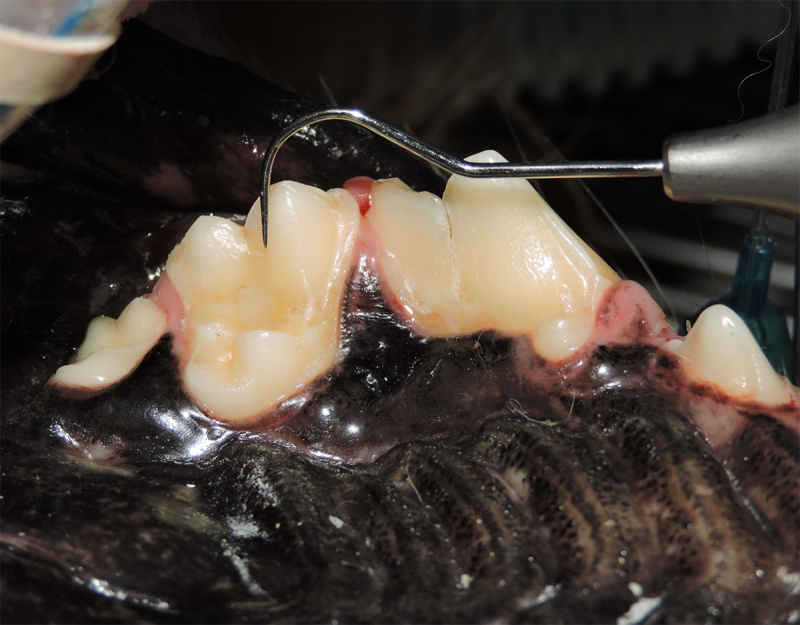

Surgical Extraction of Diseased Teeth

Periodontal disease is extremely common in dogs and cats. Over 80% of dogs and cats over two years of age have some degree of periodontal disease. Periodontal disease is best prevented by yearly professional dental cleanings starting at two years of age and at home brushing at least three times weekly. Brushing should begin at a very early age to allow your new pet to get used to regular brushing. In severe cases of infection or periodontal disease, the teeth may need to be surgically extracted. Extractions should always involve x-rays of the tooth first, as many teeth have multiple roots or may be diseased below where the eye can see. Extracting larger teeth in animals requires oral surgery, equivalent to removing wisdom teeth in people. It is vital that all of the tooth and roots be removed for the periodontal infection to resolve. In cases of important teeth with mild to moderate periodontal disease, multiple periodontal treatments can be offered to help save these teeth.